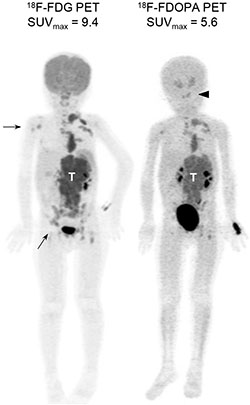

Whole-body PET scans using FDG or FDOPA provided good spatial resolution and clear contrast in the bony compartments and complement each other (Figure 1). Although the strong physiologic FDG uptake by the brain and nasopharynx interfered the interpretation of skull lesions, FDOPA PET helped to identify lesions in the head and neck region more accurately. These imaging features are consistent with our previous findings [18].

Figure 1: Diagnostic PET imaging with FDG and FDOPA. Representative maximum intensity projection images of FDG and FDOPA PET scans in a 4-year-old girl with stage 4, MYCN-amplified neuroblatoma at diagnosis. Both scans identified the main tumor (T) with multiple metastases. FDG PET detected more bony lesions in the right humerus and pelvis (arrows), while FDOPA PET provided better contrast to define skull base lesions (arrowhead).